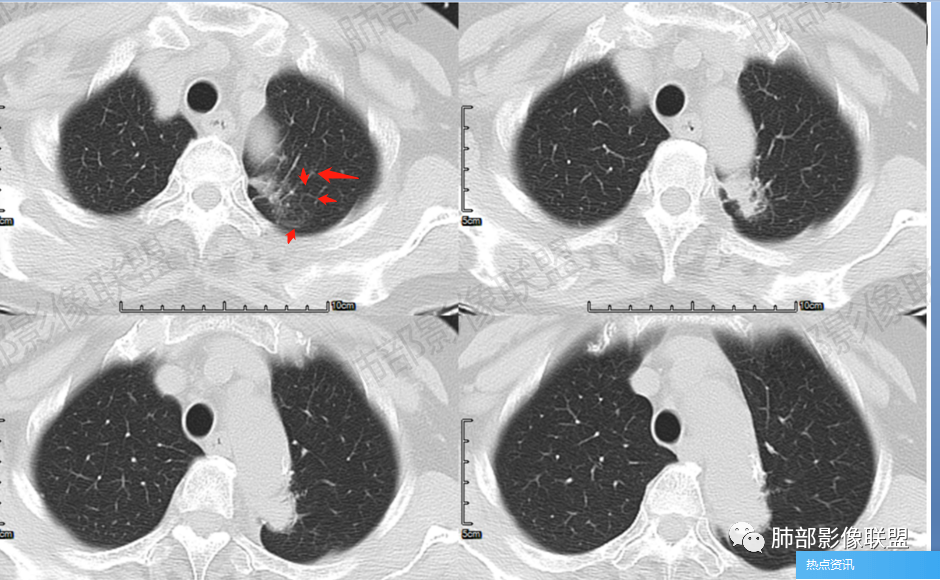

尘缘:支气管进入并堵塞

尘缘:病灶沿主动脉匍匐样生长,但整体明显膨隆,胸膜牵拉凹陷,局部有小喇叭口样改变。

尘缘:边界清楚的GGO。

尘缘:局部血管增粗,扭曲

尘缘:局部有淋巴管增粗,小叶间隔增厚,提示癌淋可能。

尘缘:最后就是强化,虽然是明显渐进性强化,要考虑炎性可能,但腺癌明显渐进性强化的并不少见。

所以,很明确的支持腺癌。

今天考虑炎性的,不外乎就是两个依据:1、强化太明显(但腺癌强化明显的不少,所以强化不是排除腺癌的依据),2、认为沿主动脉匍匐样生长,这形态应该是炎性(但马春平老师已经解释了,在特殊部位的腺癌,形态是多样化的。可以长得千奇百怪)。

2.轴位显示主动脉弓旁依势傍行弧形高密度影,隐约见尖后段支气管进入并截止。病灶边界较清楚,见血管结构及线性影与邻近肺组织相延伸。

3.病灶渐进性显著均匀强化!动脉期未见主动脉腔异常通道。

4.冠矢状位病灶于弓上部偏后局限性“贝雷帽”状突起,提示病灶有局部膨隆特点,且病灶上份及后份饰以边缘较清楚磨玻璃影。

3.如前所述本例病灶定位于尖后段肺组织,冠矢状位病灶明显局限性膨隆感,如有老师分析时称“见较清楚磨玻璃边缘”——这应当是本例较重要诊断线索!

4.病灶显著强化是符合腺癌影像学特点的。